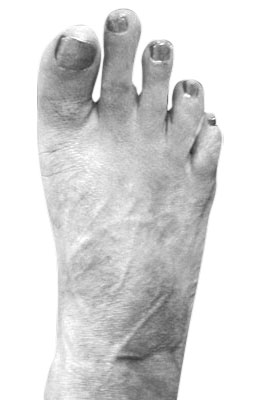

Before

Minimally Invasive Bunion Surgery before

After

Minimally Invasive Bunion Surgery after

Minimally Invasive Bunion Surgery featuring the miniBunon™ System and Tailors Bunionectomy

Melissa is a 32-year-old businesswoman who could not be off her foot post-surgery, yet she had a severely painful bunion. We performed our miniBunon™ System (our trademarked minimally invasive bunion surgery) and had a dramatic correction with no downtime. Melissa continued to work after her bunion surgery and was back in shoes and full activity at 5 weeks. Melissa could not believe the results of her Bunionectomy resulting in no bony bump, no scar and amazing motion. “After” picture taken immediately following surgery. Note the bunion and bunionette (Tailor’s bunion) in the before picture.